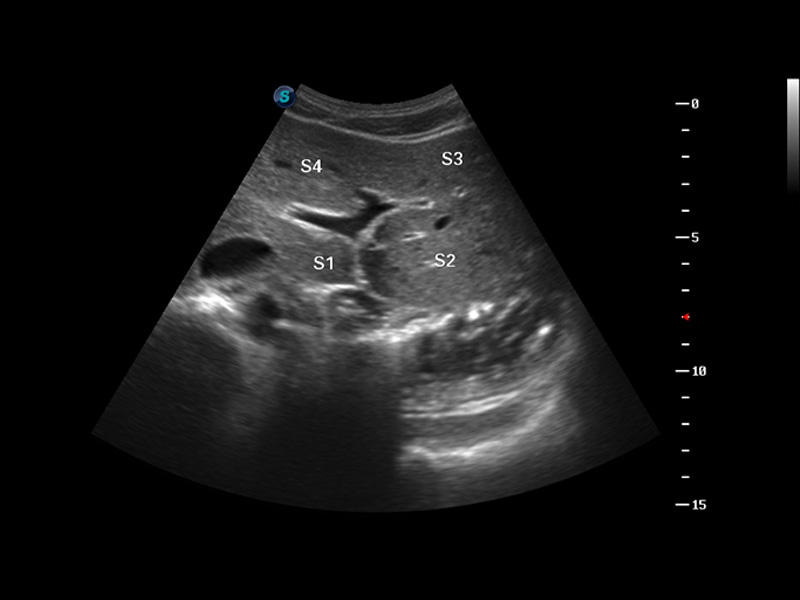

S8 EXP便携式彩色多普勒超声诊断仪是哈哈体育官网研发的高端全身应用型便携彩超。高通道的VIS平台融合可视化(Visual)、智能化(Intelligent)和人性化(Smart)的特点,配以哈哈体育官网自主研发生产的探头大家族,使您能够快速、准确的获得病人信息,提高工作效率的同时减轻疲劳。

μ-Scan微米成像

谐波成像

空间复合成像

3D/4D成像